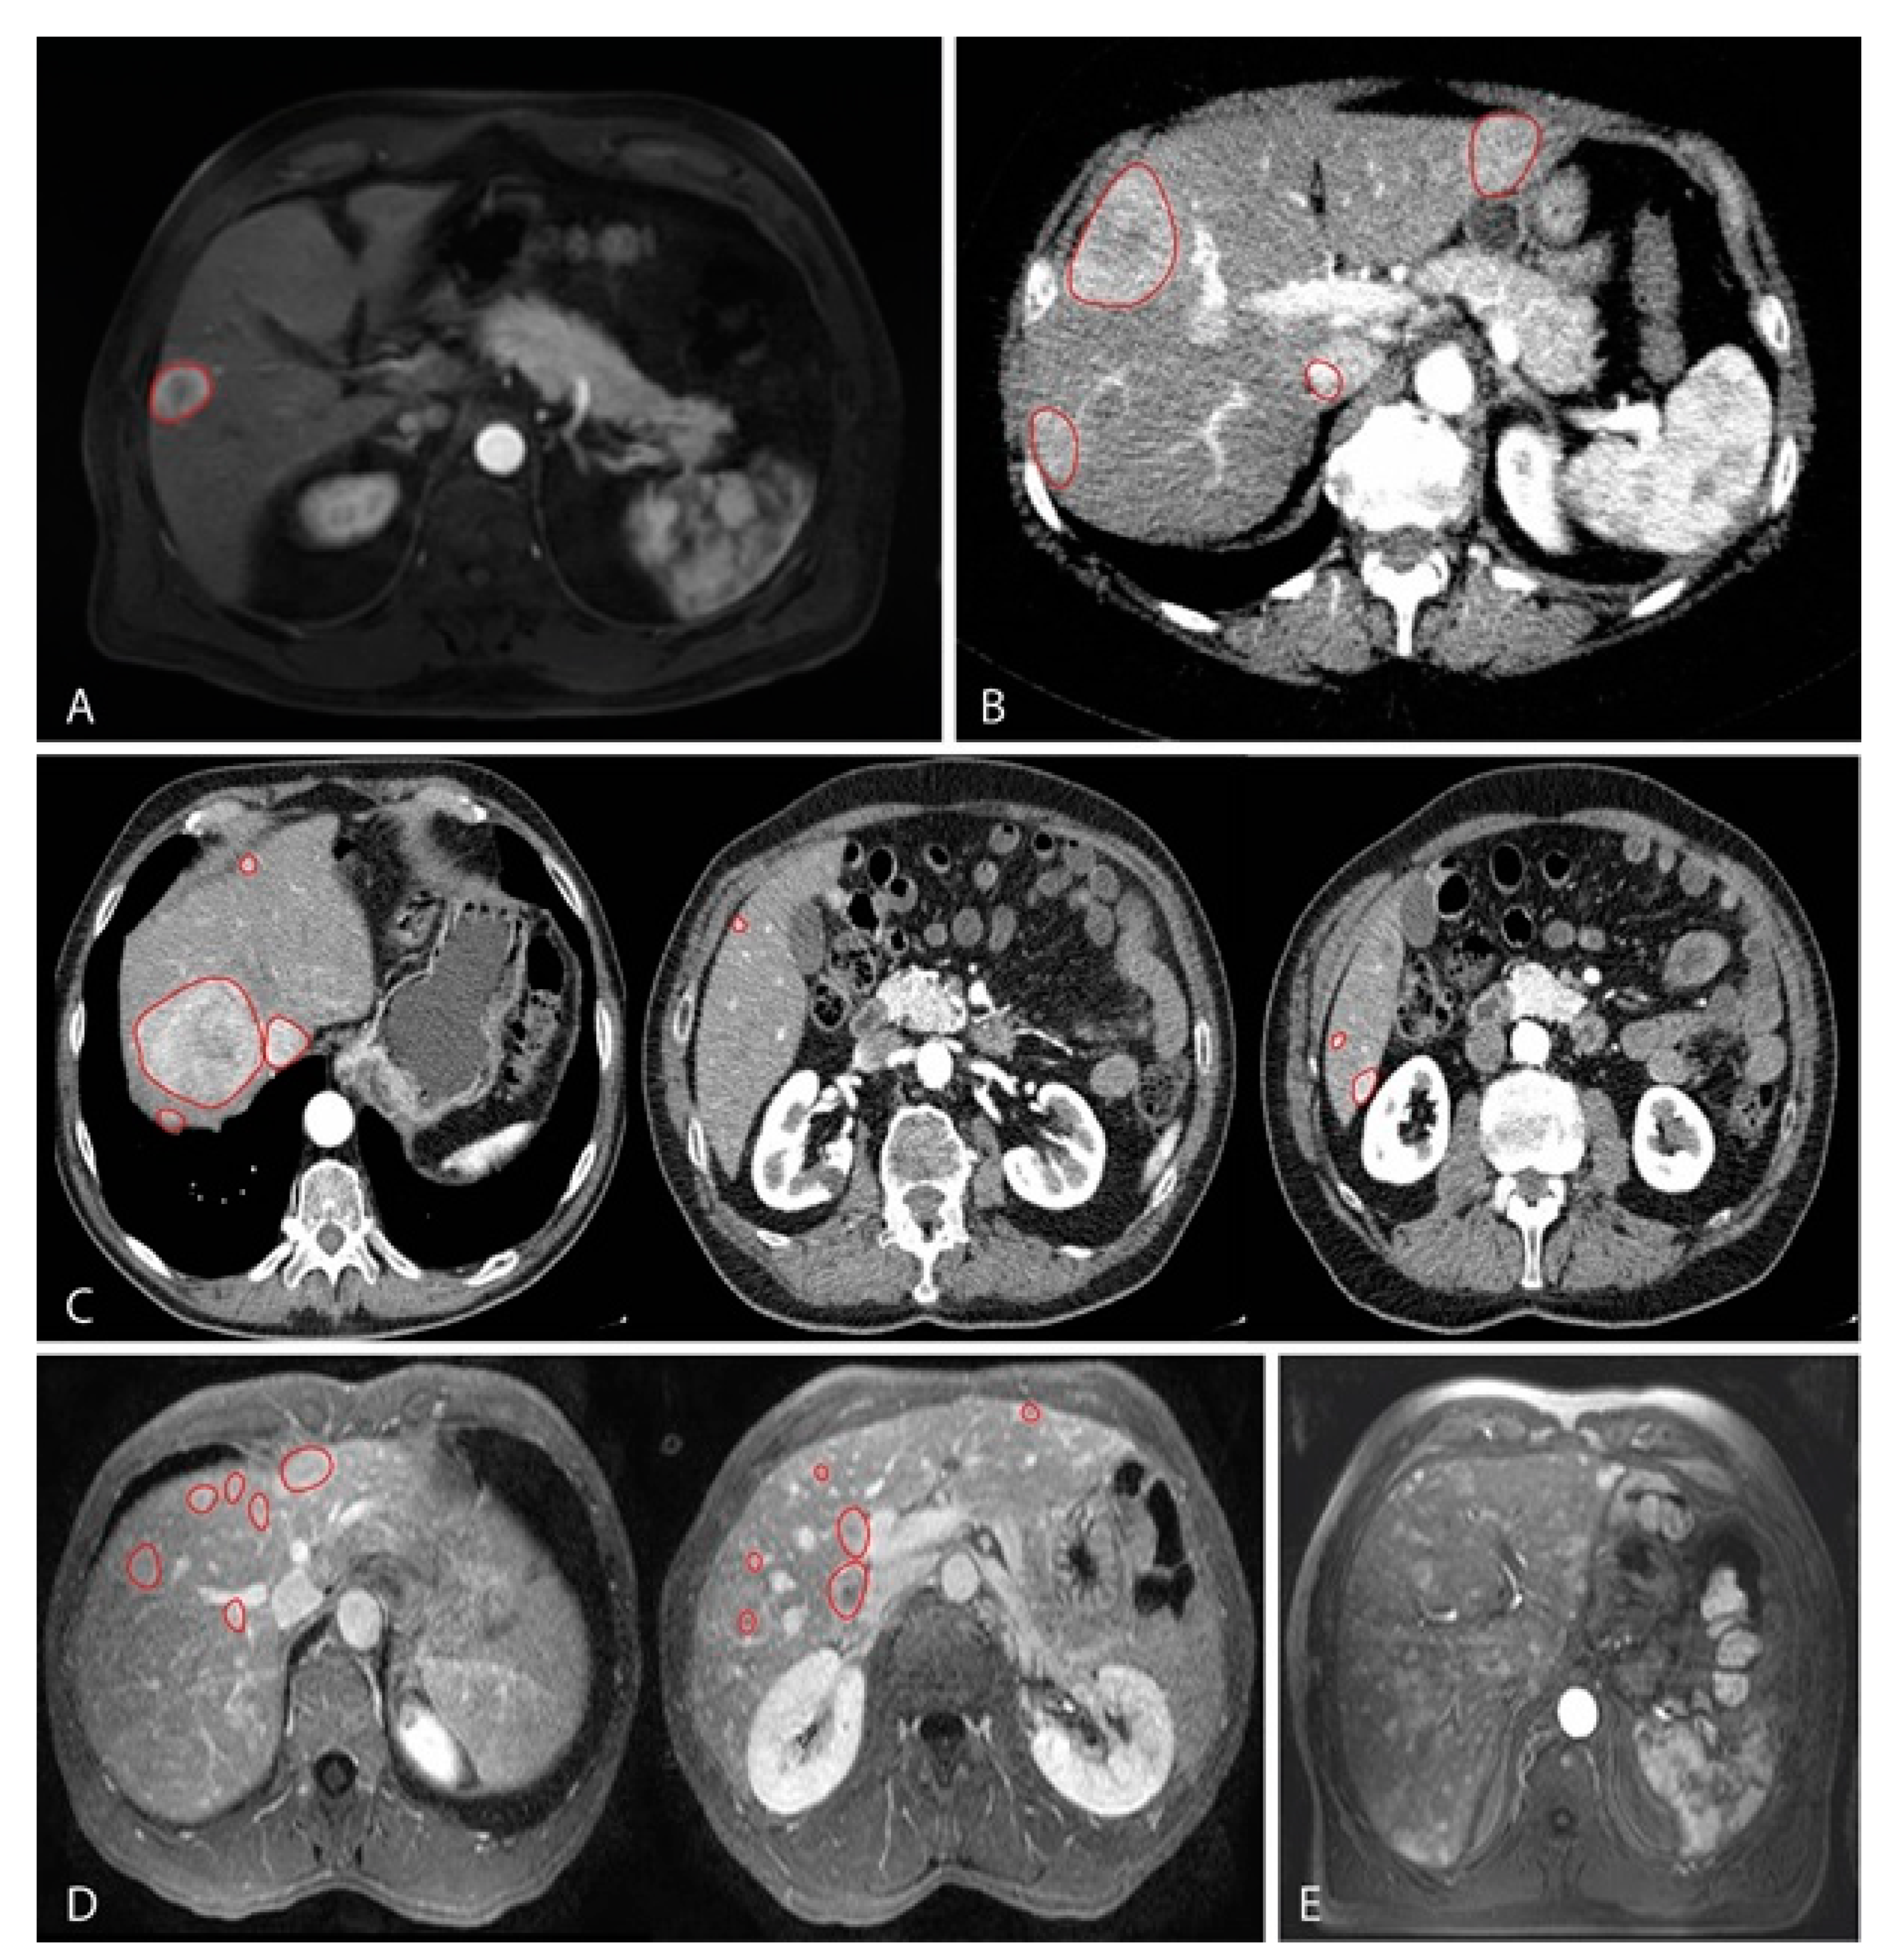

Classification of CT or MRI images were based on the total amount of hepatic metastases, this resulted in the following groups: single nodular lesion (Figure 1A), between 2 and 5 lesions (Figure 1B), between 6 and 10 lesions (Figure 1C) and more than 10 lesions (Figure 1D). Survival analyses were performed by using at the time from diagnosis up until metastatic disease (DFS) and survival with metastatic disease.

MRI images representing the classification based on the number of lesions found in metastatic UM in the liver, which have been contrasted by red markings; (A) T1 weighted MRI with contrast showing a single nodular lesion in the liver; (B) T2 weighted MRI with contrast showing four lesions; (C) T2 weighted MRI sequence with contrast showing a total of seven lesions. Images from left to right correspond, respectively, from cranial to caudal localization; (D) T2 weighted MRI sequence with contrast showing a total of 12 lesions. Images from left to right correspond, respectively, from cranial to caudal localization; (E) T2 weighted MRI with contrast showing innumerable widespread small lesions throughout all liver segments. No red markings are present due to the number of lesions.

We observed a difference for DFS when comparing all groups (p = 0.009; Figure 2A). This showed a shorter DFS with increasing number of hepatic metastases. We also analyzed using thresholds rather than separate groups. These were set on one solitary lesion versus more than one (1 vs. >1); five or less versus more than five (≤5 vs. >5); 10 or less versus more than 10 lesions (≤10 vs. >10). Each time the DFS was worse in patients with more metastases (p = 0.038, p = 0.001 and p = 0.003, respectively; Figure 3B, Figure 3c and Figure 3D). Histopathologically there are distinctive liver growth patterns in metastasized UM; the nodular and infiltrative growth patterns [23,24]. The infiltrative growth pattern is characterized by many metastases that are up to 50 µm large [23,24]. This pattern of innumerable small metastasis is also named miliary pattern on CT and MRI images. Upon reviewing CT and MRI images of the >10 lesions group (n = 53), we divided this group into two separate groups. A group (n = 29) containing samples with more than 10 lesions (larger than 50 µm; Figure 1D) and a group (n = 24) containing samples with a miliary pattern (innumerable lesions smaller than 50 µm; Figure 1E). Comparing both groups did not show a significant difference in DFS (p = 0.375).